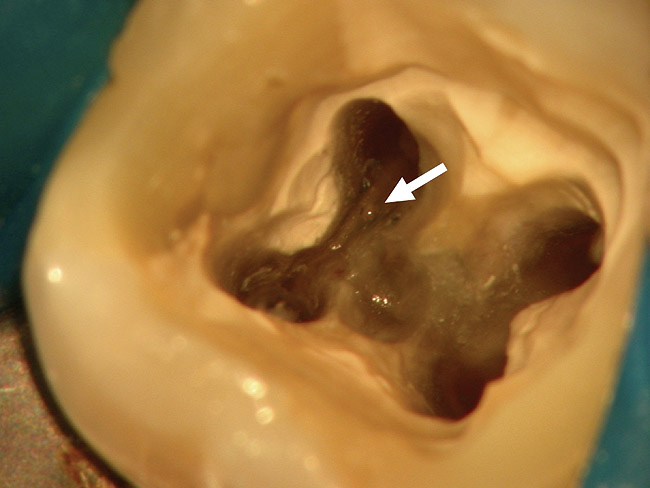

Figure 4b  The patient was asymptomatic, and periodontal probing depths were within normal limits; however, a new crown restoration was planned. Nonsurgical endodontic re-treatment was initiated. The intracoronal picture shows the previously treated 4 canals with infected gutta-percha filling.

Figure 4b

Figure 4c  Under high magnification, a furcation canal (Figure 4C) and a third distal canal (Figure 4D) were located.

Figure 4c

Figure 4d  Under high magnification, a furcation canal (Figure 4C) and a third distal canal (Figure 4D) were located.

Figure 4d